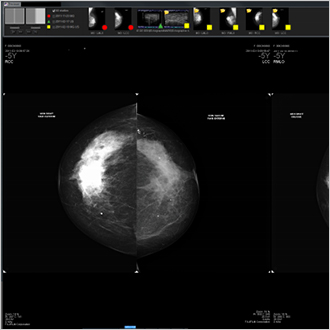

TM-Mammo

Die Lösung TM-Mammo wurde speziell als Antwort auf die Anforderungen an die Speicherung, Verteilung und Diagnose der gesamten digitalen Mammografiebilder entwickelt, die im Rahmen der Brustheilkunde aufgenommen werden. Der Viewer TM-Mammo ermöglicht den einfachen Vergleich mit mehreren Bildern (aller Arten und Modalitäten) aus der Krankengeschichte der Patientin und die Anzeige von benutzerdefinierten Ansichtssequenzen. Die Tomosynthese ist integraler Bestandteil der Ansichtssequenzen.